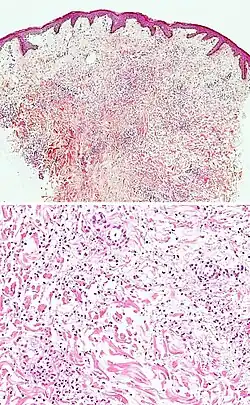

| Secondary syphilis | Various, but often one or a combination of:[21]

|